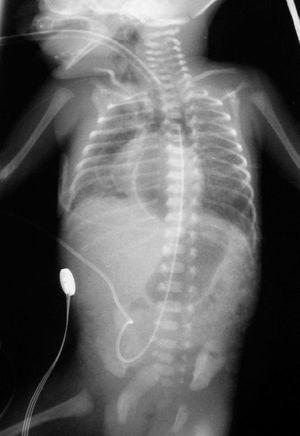

En los días siguientes, el cuadro respiratorio empeoró, apareció un enfisema subcutáneo con aparición de un enfisema intersticial en la radiografía de tórax (fig. 1), y se instauró ventilación de alta frecuencia. Posteriormente, pudo pasar de nuevo a VMC, y fue extubado 24 h después, aplicándose presión positiva continua en la vía aérea por vía nasal (n-CPAP). El neumomediastino persistió sin neumotórax asociado.

Figura 1. Radiografía de tórax y abdomen. Se observa la existencia de un neumomediastino con enfisema intersticial y enfisema subcutáneo en la faringe.